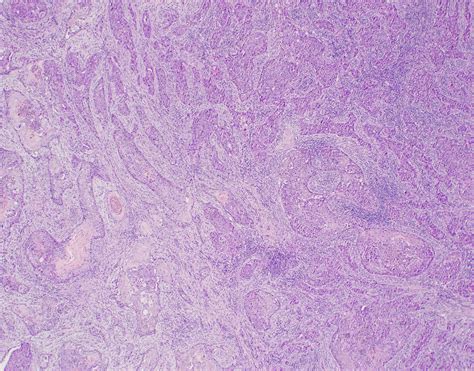

Think of it like this: you see a shadow on the wall and think it’s a monster, but it’s actually just your coat hanging up. Same idea – you need to know what you’re really dealing with before you react. In the context of cancer, getting this right can significantly impact a patient’s quality of life and treatment outcomes. Doctors use a range of diagnostic tools, including imaging (like CT scans and MRIs) and biopsies, to differentiate between true metastasis and pseudometastatic conditions. They also look at the specific characteristics of the cells under a microscope, using techniques like immunohistochemistry to identify specific markers.

The diagnostic process is complex. Doctors use a combination of imaging techniques, biopsies, and molecular testing to understand exactly what’s going on. Imaging helps them visualize the extent of the apparent spread, while biopsies allow them to examine the cells under a microscope. Molecular testing can identify specific markers that distinguish between different types of cancer and even differentiate between true metastasis and pseudometastatic conditions. For example, immunohistochemistry can detect the presence or absence of certain proteins that are characteristic of specific types of cancer. These markers can help confirm whether the cells in question are actually cancerous and whether they originated from the primary tumor site or somewhere else.

• Immunohistochemistry (IHC): This technique uses antibodies to detect specific proteins in the tissue sample. It can help identify the type of cancer and even predict how it will respond to treatment.